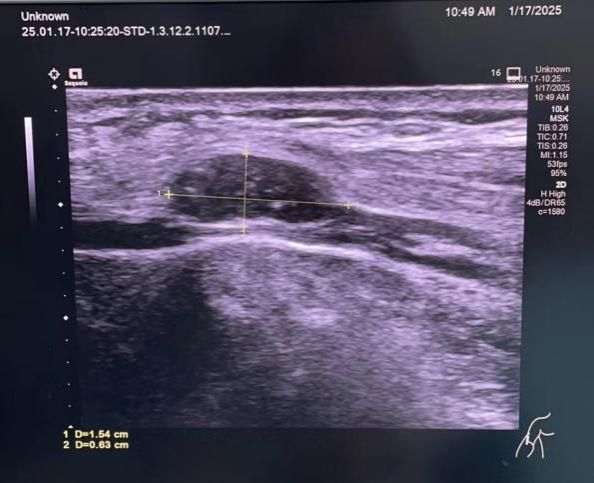

在李浩鹏主任、王栋主任的领导和支持下,脊柱与骨肿瘤病区(原骨二科)已成为陕西以及周边省区血友病患者的骨科手术中心。近日一位血友病患者专门来脊柱与骨肿瘤病区张廷副主任医师门诊就诊,要求手术。这位患者的肘部有一个肿物压迫尺神经,引发显著的手部疼痛、麻木、无力,已经严重影响了患者的日常工作和生活。但因为这位患者伴发高滴度抑制物,之前已辗转多家医院求治不果。血友病伴发高滴度抑制物,围手术期的出凝血管理是手术成功的关键。张廷副主任医师、李京住院医师讨论后,结合我国国情和患者实际情况,选择了重组活化人凝血因子VII和凝血酶原复合物交替使用的止血方案。临近春节,我院药学部加速审批,迅速从全国跨区域调配来稀缺药品重组活化人凝血因子VII。手术中,张廷、李京医生显微精细操作,在完整切除肿瘤的同时,保全了神经,并做到了充分止血,降低了术后出血的可能。术后止血是重中之重。如何精准地调整重组活化人凝血因子VII和凝血酶原复合物的用法用量,实现彻底止血和防止血栓形成之间的平衡,保障患者安全的同时合理控制花费,是一个重大的考验。春节八天假期是患者术后治疗的关键期,张廷、李京医生春节假期轮流来院,及时调整患者的治疗方案,保证了假期患者治疗不松劲。患者术后未发生过量出血,未发生血栓事件,症状显著缓解,伤口已顺利愈合。术后病理结果回报为纤维瘤。

这位患者的治疗工作受到了我院血液内科雷博教授、西安市中心医院血液内科宋艳萍教授、李光教授、我院药学部张丽娜、陈晓敏老师、我院超声科李苗教授、崔毅鹏老师、检验科雷娜老师的指导和支持。